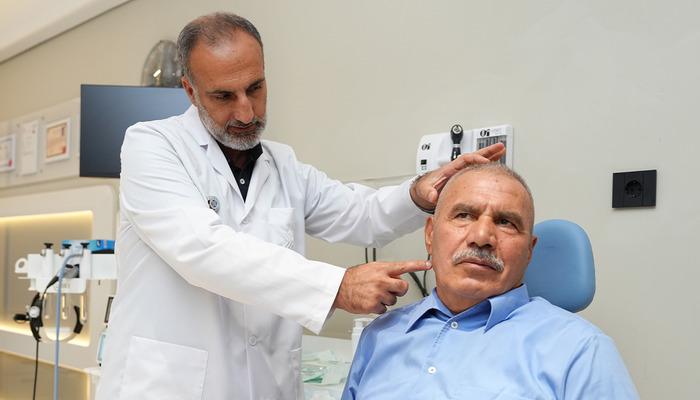

‘Önemli değil’ dediği tümör hayatını kabusa çevirdi: Yüzündeki şiddetli ağrı yüzünden yemek yiyemez hale geldi: Kulak tümörü kaynaklı çıktı!